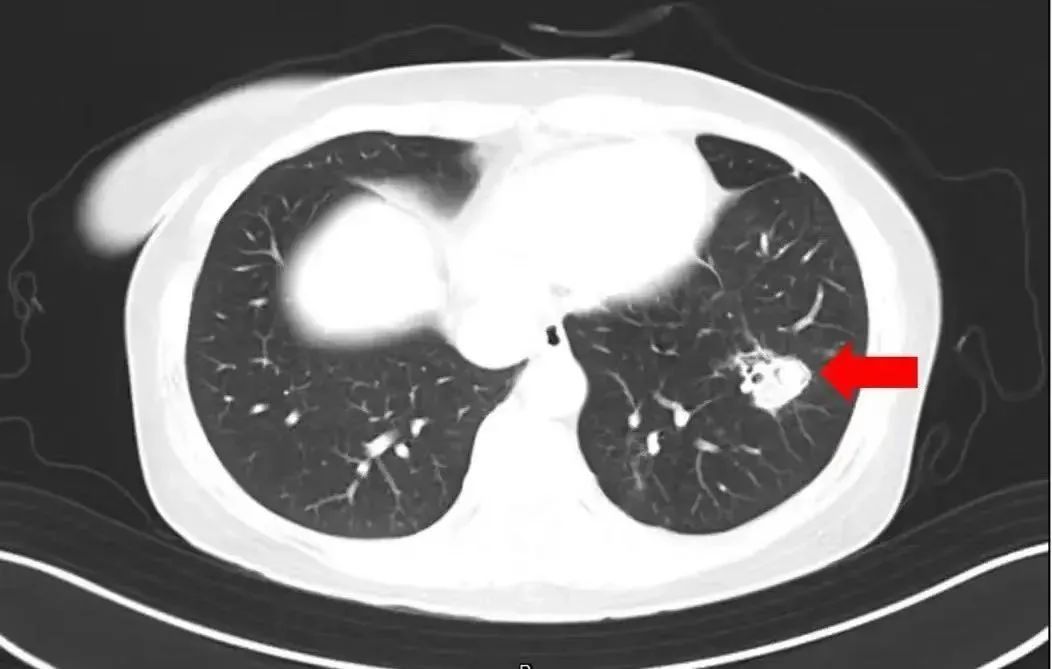

在了解情况后,医生为她做了纤维支气管镜检查及肺泡灌洗液病原体检测,果然发现气道壁上有大量白色菌斑,这就是引起患者高烧、咳嗽的“元凶”——肺曲霉菌病。